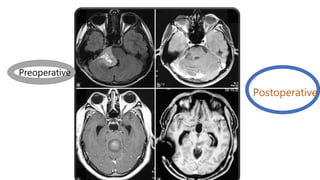

Pre-

operative

Postoperative

Preoperative

Surgical approaches andtechniques • Preoperative stereotactic imaging to guide the surgical approach in order to minimize manipulation of normal tissue and maximize tumor resection • Intraoperative MRI imaging, including functional MRI to aid in intraoperative decision making • Intraoperative MRI imaging, including functional MRI to aid in intraoperative decision making • Postoperative imaging, preferably by MRI, is performed within the first 24 to 72 hours

Preoperative and perioperativeconsiderations 1. Increased intracranial pressure (ICP) including obstructive hydrocephalus 2. Seizures 3. Endocrine abnormalities

From the “noman's land” to the “safe entry zone”, the surgical management of brainstem gliomas has seen a lot of tectonic shifts.